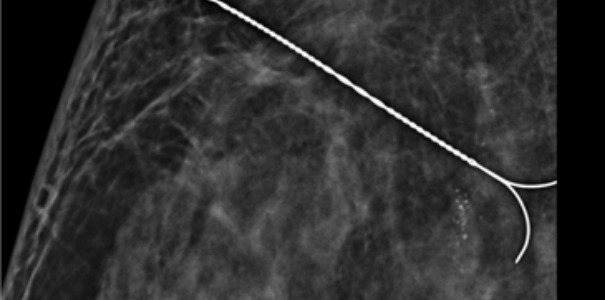

이런 경우 예전에는 갈고리형의 침을 꽂아 유방에 넓은 부위를 절개하여 조직검사를 진행했으나

본 원에서는 진공흡인 보조장치(맘모톰)를 통해 특수한 바늘로 병변 위치, 크기 등을 세밀히 확인할 수 있고(침 위치 결정 술)

해당 병변 조직을 채취하여(조직검사) 빠른 시일 내 암 또는 양성 결절(혹, 종양)을 진단 할 수 있게 되었습니다.

유방 조직구조가 뒤틀리고 왜곡된 현상만 발견되고 유방촬영, 유방초음파 검사상 암 진단 관련하여 이상소견이 보이지 않았으나

진공흡인 보조장치(맘모톰) 특수바늘을 통해 병변 확인 및 조직 채취 후 암 진단 판정되어 치료 진행

치밀유방 여성, 우측 미세석회 발견

진공흡인 보조장치(맘모톰) 조직 채취 후

암 진단 판정